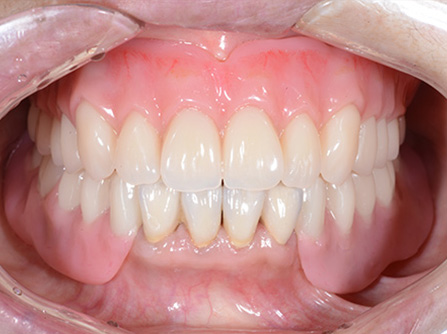

症例1

歯がグラグラで噛めない。自然な入れ歯で綺麗にしたい。という主訴でご来院頂いた患者様に対して特殊プラスチックを使用した総入れ歯(入れ歯)とコーヌスクローネ義歯(入れ歯)の症例

術前

入れ歯での治療後

どこが入れ歯かわかりますか?

(このページの最後に正解があります)

入れ歯の一番の悩みとして『見た目が悪い』。中でも前歯のワイヤーが嫌な方が多くおられます。トップの歯の写真を見てください。奥歯に少し金属が見られますが、唇で隠れるところなので、患者様は全く気にならずに、お友達とお食事や会話を楽しんでおられます。